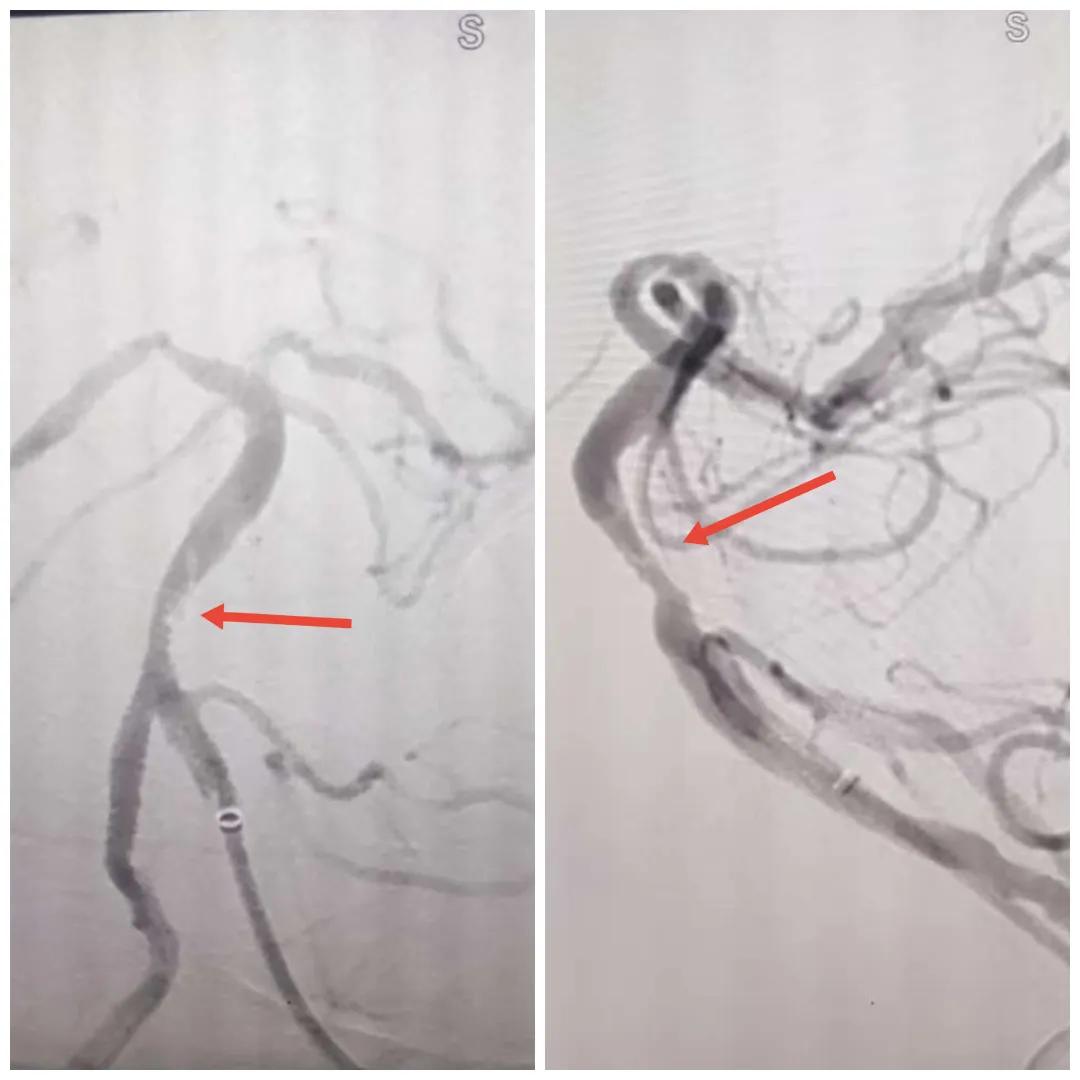

在經(jīng)造影后,主刀醫(yī)生腦一科副主任楊慶堂發(fā)現(xiàn)患者基底動脈下段重度狹窄且狹窄段以遠有大負荷血栓,其狹窄處考慮為動脈夾層,手術(shù)難度及風險較大。楊慶堂副主任在彭壯副主任醫(yī)師的協(xié)助下運用spaceman(太空人)技術(shù),中間導管抵近血栓抽吸配合支架拉栓,成功開通血管。再次造影可見基底動脈管腔明顯增寬,遠端血管顯影良好,且等待20分鐘后造影仍顯示血流通暢。楊慶堂副主任考慮到本次手術(shù)時間不宜過長,現(xiàn)患者基底動脈及分支前向血流維持良好,給予其抗栓藥物應用后結(jié)束手術(shù),并建議患者3個月后復查造影,明確其基底動脈夾層情況。

取栓后血管管腔增寬,前向血流良好